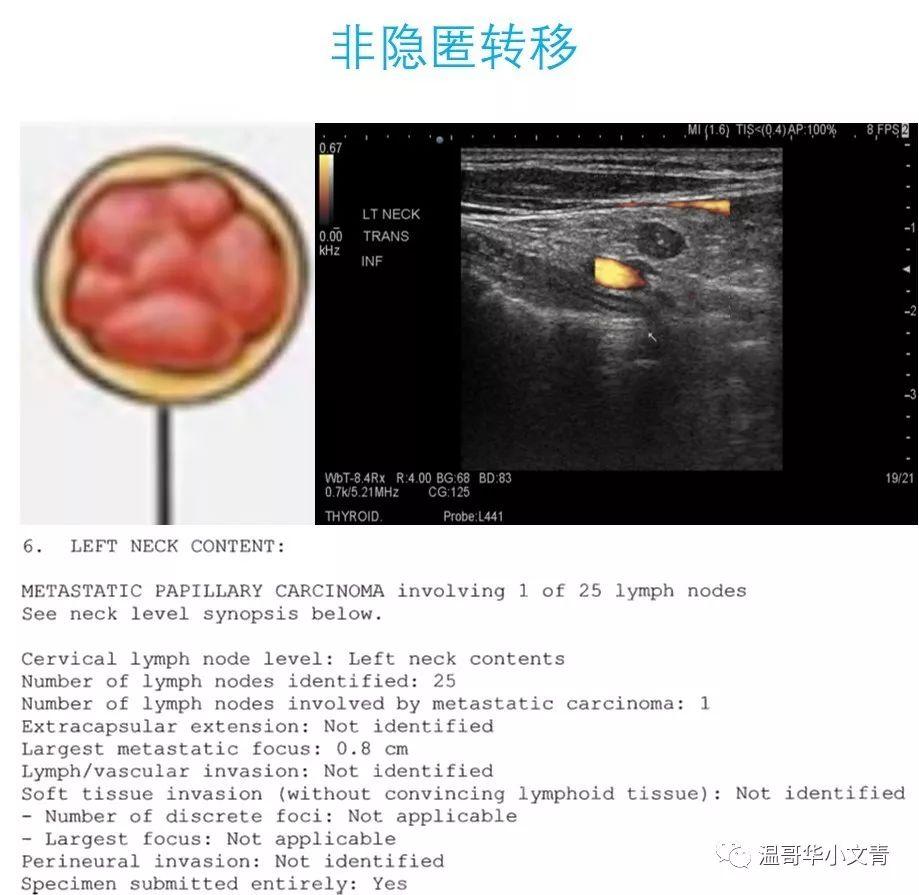

三大奇葩说甲状腺癌的淋巴结转移 – 知乎